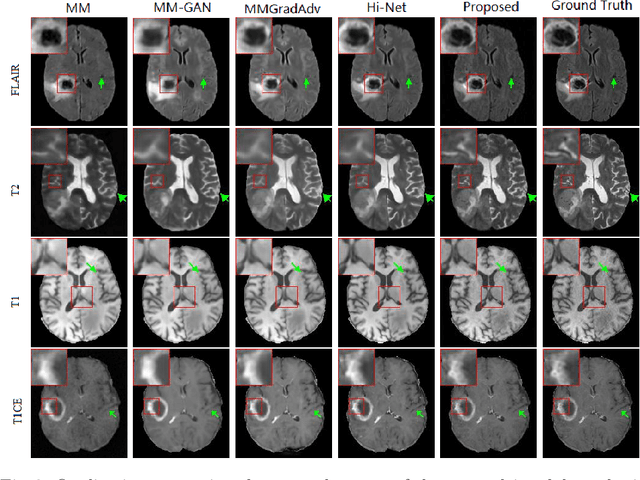

Generating multi-contrasts/modal MRI of the same anatomy enriches diagnostic information but is limited in practice due to excessive data acquisition time. In this paper, we propose a novel deep-learning model for joint reconstruction and synthesis of multi-modal MRI using incomplete k-space data of several source modalities as inputs. The output of our model includes reconstructed images of the source modalities and high-quality image synthesized in the target modality. Our proposed model is formulated as a variational problem that leverages several learnable modality-specific feature extractors and a multimodal synthesis module. We propose a learnable optimization algorithm to solve this model, which induces a multi-phase network whose parameters can be trained using multi-modal MRI data. Moreover, a bilevel-optimization framework is employed for robust parameter training. We demonstrate the effectiveness of our approach using extensive numerical experiments.